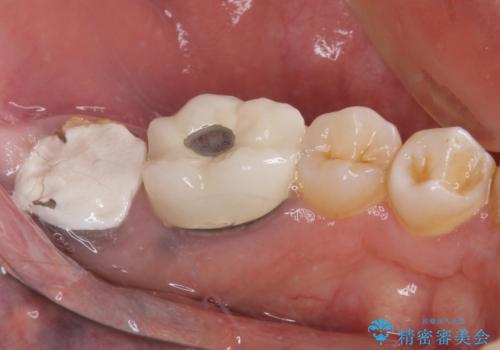

抜歯が必要な奥歯 ストローマン・インプラント補綴治療

- 近医にて奥歯の抜歯が必要と言われたとのことで来院された患者様です。

診査の結果、歯が破折しており、抜歯が必要な状態でした。

最後方歯であるため、入れ歯かインプラントかどちらかの補綴治療を行うこととなりますが、ご希望によりインプラント補綴治療を行うこととしました。

インプラントにはストローマン社のSLActiveを使用し、埋入から補綴までおよそ3か月と、短期間で治療を進めることができました。